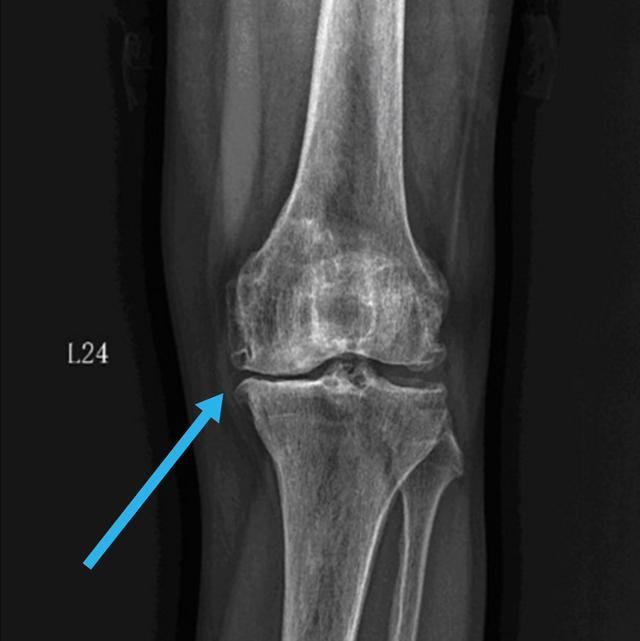

如图所示,内侧关节缝隙比外侧变得狭窄了,膝盖的外观也就变成罗圈腿了。当出现这些症状的时候,我们就会开始出现走路疼痛。一般都是先有内侧疼,然后逐渐发展到整个关节都疼。等到走平地都不能走了,每一步都疼的时候,往往这个时候就需要做保膝手术或关节置换等手术治疗了。除此之外呢,我们的膝盖还有一个关节面,叫做髌股关节。也就是刚才我们摸的那个圆骨头深部的软骨面。这个部位比较特殊,当我们伸直腿,也就是走路的时候,这个关节面的压力是比较小的,甚至软骨和软骨之间都是不接触的。这是为什么刚才我们在伸直并放松大腿肌肉的时候,髌骨可以推动的原因。